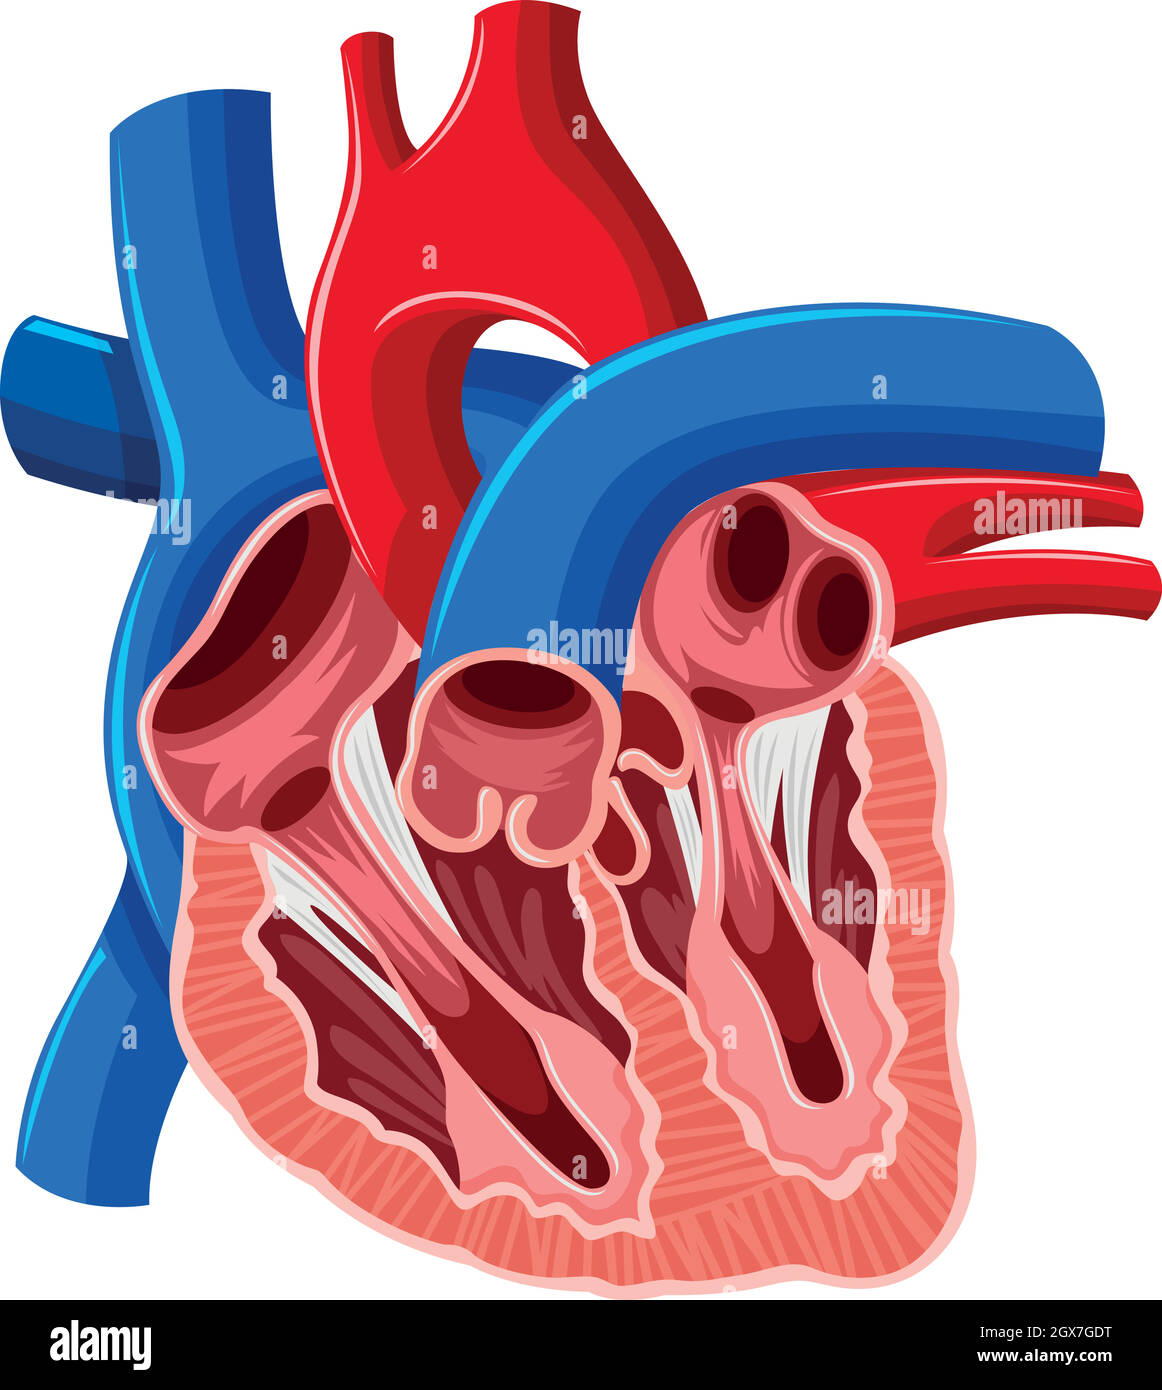

Inside diagram of human heart Stock Vectorhttps://www.alamy.com/image-license-details/?v=1https://www.alamy.com/inside-diagram-of-human-heart-image446406852.html

Inside diagram of human heart Stock Vectorhttps://www.alamy.com/image-license-details/?v=1https://www.alamy.com/inside-diagram-of-human-heart-image446406852.htmlRF2GX7GDT–Inside diagram of human heart